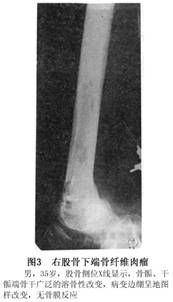

X线检查:骨纤维肉瘤的X线特点是:①呈地图形、虫蚀型、穿凿型溶骨性骨破坏,一般由正常骨质到病变骨质之间的转化带宽。②很少有骨硬化及骨膜反应,若有骨膜反应,可以表现为板层样、放射状及Codman三角。同时可有骨皮质破坏及软组织包块(图3)。

在管状骨纤维肉瘤可位于中心或偏心。在管状骨内纤维肉瘤,如果呈偏心位,病变呈地图样破坏,而且仅侵及部分骨皮质,其预后较没有这些特点者好。

实际上骨纤维肉瘤的X线异常并无特别的特异性。一般给人的印象是一个侵袭性或者恶性病变。由于病变中没有钙化及骨化的表现,根据这一点可以和骨肉瘤及软骨肉瘤相鉴别。但纤维肉瘤如与恶性纤维组织细胞瘤、毛细血管扩张骨肉瘤、淋巴瘤、浆细胞骨髓瘤和骨转移瘤相鉴别,则有一定困难。有时其他影像学方法可以提供更多一些资料,但是没有特殊诊断意义。